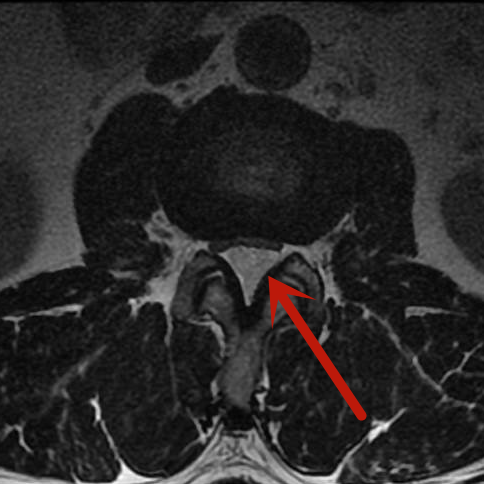

在完善術前檢查,排除手術禁忌,充分做好術前準備后,該手術由微創手術經驗豐富的羅同青副主任醫師主刀。經過2個多小時,患者的腫瘤被完整切除,術中出血約20ml,手術十分成功。術后病理結果回報證實為椎管內血管瘤。

術后影像

術后第1天,梁先生便可下床活動,沒有出現手術并發癥。3天后,梁先生就康復出院了,他激動地說:“感謝市人民醫院脊柱骨科團隊,一個小小的切口就解決了我的大麻煩,你們的醫術真精湛!”